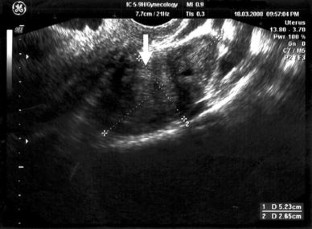

We report the fourth case of ovarian adenomyoma in a 45-year-old woman with an endometrial polyp. Transvaginal ultrasonography revealed a solitary endometrial polyp with an enlarged left ovary which appeared heterogenous with isoechoic and mildly hyperechoic pattern.

Fig. 5